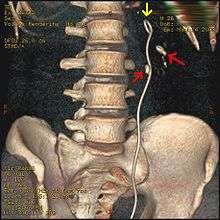

Otherwise a noncontrast helical CT scan with 5 millimeters (0.2 in) sections is the diagnostic modality of choice in the radiographic evaluation of suspected nephrolithiasis.[12][42][45][46][3] All stones are detectable on CT scans except very rare stones composed of certain drug residues in the urine,[47] such as from indinavir. Calcium-containing stones are relatively radiodense, and they can often be detected by a traditional radiograph of the abdomen that includes the kidneys, ureters, and bladder (KUB film).[47] Some 60% of all renal stones are radiopaque.[45][48] In general, calcium phosphate stones have the greatest density, followed by calcium oxalate and magnesium ammonium phosphate stones. Cystine calculi are only faintly radiodense, while uric acid stones are usually entirely radiolucent.[49]

Where a CT scan is unavailable, an intravenous pyelogram may be performed to help confirm the diagnosis of urolithiasis. This involves intravenous injection of a contrast agent followed by a KUB film. Uroliths present in the kidneys, ureters or bladder may be better defined by the use of this contrast agent. Stones can also be detected by a retrograde pyelogram, where a similar contrast agent is injected directly into the distal ostium of the ureter (where the ureter terminates as it enters the bladder).[45]

Ultrasound imaging of the kidneys can sometimes be useful, as it gives details about the presence of hydronephrosis, suggesting the stone is blocking the outflow of urine.[47] Radiolucent stones, which do not appear on KUB, may show up on ultrasound imaging studies. Other advantages of renal ultrasonography include its low cost and absence of radiation exposure. Ultrasound imaging is useful for detecting stones in situations where X-rays or CT scans are discouraged, such as in children or pregnant women.[50] Despite these advantages, renal ultrasonography in 2009 was not considered a substitute for noncontrast helical CT scan in the initial diagnostic evaluation of urolithiasis.[46] The main reason for this is that compared with CT, renal ultrasonography more often fails to detect small stones (especially ureteral stones), as well as other serious disorders that could be causing the symptoms.[10] A 2014 study confirmed that ultrasonography rather than CT as an initial diagnostic test results in less radiation exposure and did not find any significant complications.[51]